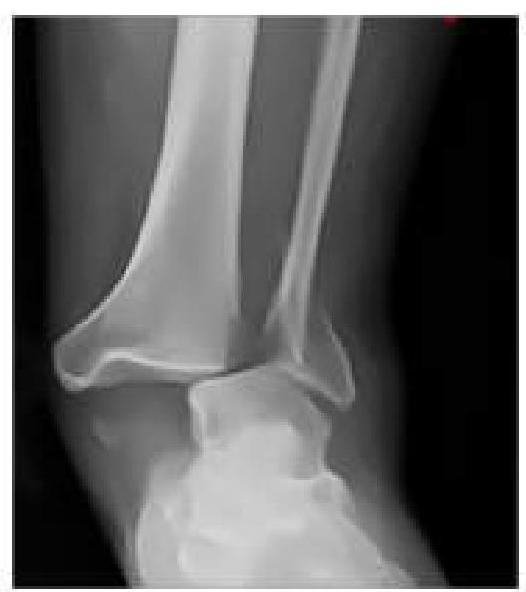

An RTA patient presented to the emergency department with severe pain in the ankle. An X-ray was performed, given below. What is the best next step in management?